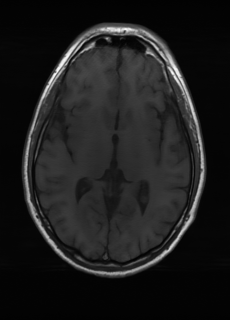

Sequence LR SISO MIMO MIMO tuned GT

λT1=6.63subscript𝜆subscript𝑇16.63\lambda_{T_{1}}=6.63 Refer to caption (a) 34.38/0.9371 Refer to caption (b) 42.42/0.9883 Refer to caption (c) 44.60/0.9920 Refer to caption (d) 45.50/0.9940 Refer to caption (e) PSNR/SSIM

λT2=2.11subscript𝜆subscript𝑇22.11\lambda_{T_{2}}=2.11 Refer to caption (f) 29.74/0.8903 Refer to caption (g) 36.25/0.9734 Refer to caption (h) 36.42/0.9752 Refer to caption (i) 37.70/0.9832 Refer to caption (j) PSNR/SSIM

λflair=8.00subscript𝜆𝑓𝑙𝑎𝑖𝑟8.00\lambda_{flair}=8.00 Refer to caption (k) 39.89/0.9311 Refer to caption (l) 43.94/0.9864 Refer to caption (m) 44.74/0.9883 Refer to caption (n) 45.49/0.9894 Refer to caption (o) PSNR/SSIM

Figure 3: Visual comparison of different methods, with PSNR (dB) and SSIM values listed under the images. After recovery, the images are shaper with more visible details.